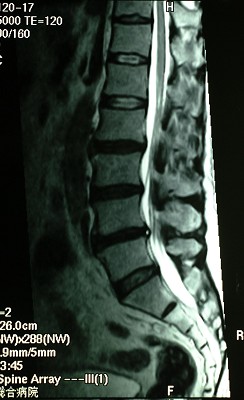

腰部のMRI

こちらも圧迫しています